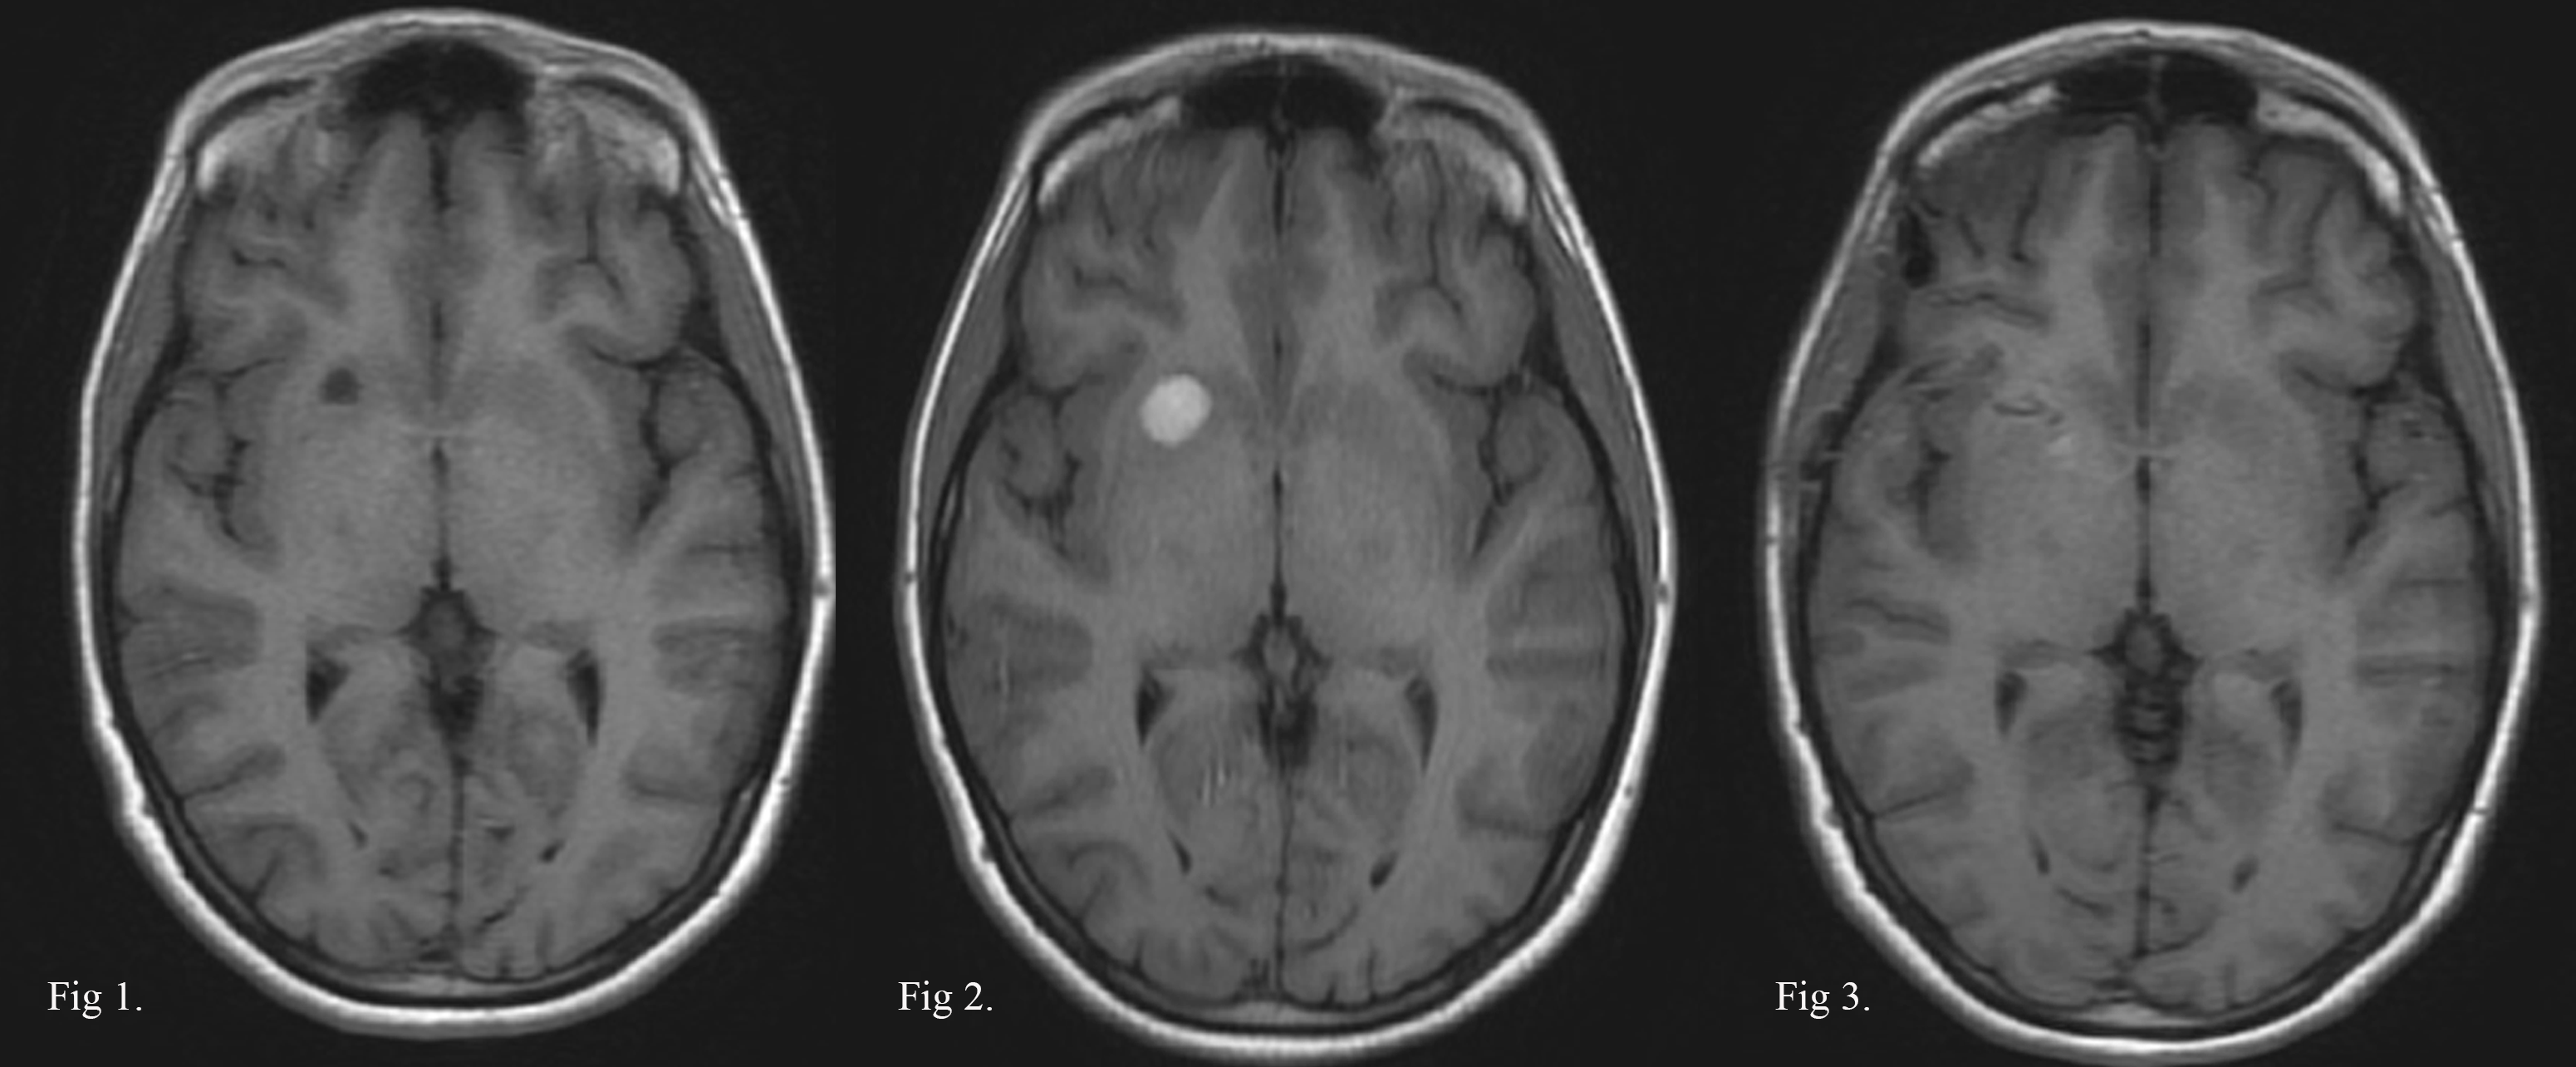

CASO EJEMPLO 1: CAVERNOMA INCIDENTAL LENTICULAR ANTERIOR DERECHO.

Fig 1: 2020: Mujer, 33 años, cavernoma incidental no complicado.

Fig 2: 2021: Persiste asintomática con hematoma intracapsular en RMN control.

Fig 3: 2021: RMN postop. de exéresis por vía transilviana trans-surco circular anterior de la ínsula.